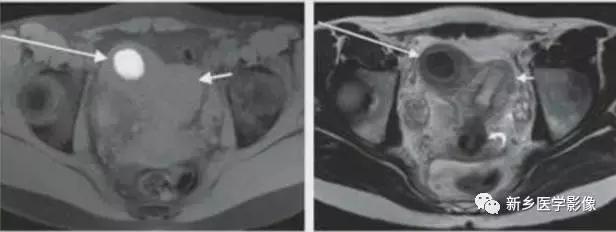

V:纵隔子宫

左图:完全纵隔子宫,纵隔延伸至宫颈内口。

中图:部分纵隔子宫,纵隔未达宫颈内口。

纵隔子宫:宫底轮廓凸出、平坦、轻度凹陷<1cm,肌壁或纵隔深入内膜腔>1cm。

弓形子宫:宫底轮廓凸出、平坦、轻度凹陷<1cm,肌壁或纵隔深入内膜腔<1cm。

完全型纵隔子宫:短T2信号纵隔贯穿宫腔,宫颈管及阴道上段。

MR诊断为完全型纵隔子宫伴阴道纵隔。